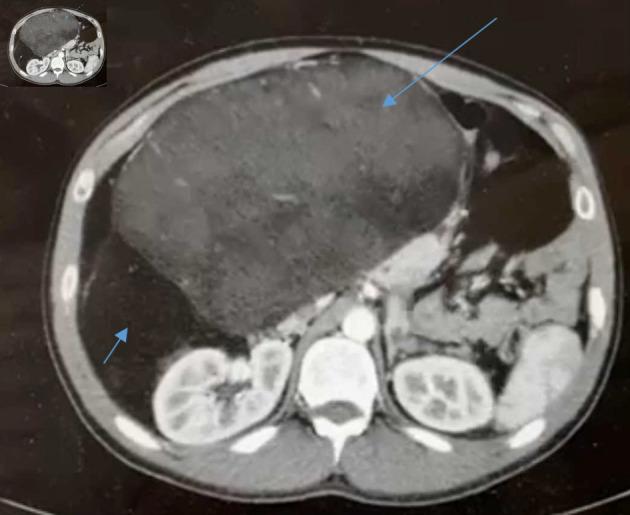

Retroperitoneal tumors (RPTs) are very rare tumors that arise in the large space of the retroperitoneum. About two-third of these tumors are malignant, of which soft tissue sarcoma (STS) is the most common and comprises almost one-third of malignant RPTs. Twenty to thirty percent of RPTs are benign. The retroperitoneal cavity has a very large potential space for tumor enlargement to a very high diameters without causing specific symptoms, especially during the initial phase of tumor enlargement. On diagnosis, the average tumor weight is 15 - 20 kg and tumor diameter is 20 - 25 cm. The most common retroperitoneal sarcoma type is liposarcoma, which account for 20% of all sarcoma types and 40% of all retroperitoneal sarcomas (RPSs). Other less common STS arise in the retroperitoneum include leiomyosarcoma and undifferentiated pleomorphic type. Giant liposarcoma is usually defined either as tumor diameter of 30 cm or more or tumor weight of 20 kg or higher. This specific type of sarcoma is very uncommon, with few case reports published in the English literature. Herein, we present a case of a healthy 33-year-old male patient, who was admitted due to abdominal distension and increased body weight since few months. An abdominopelvic computed tomography (CT) scan demonstrated a giant retroperitoneal mass of almost 40 cm in diameter in its largest dimension, located in the right retroperitoneal space. Ultrasound (US)-guided fine needle biopsy (FNB) was consistent with well differentiated liposarcoma. Surgical resection of the tumor along with the right colon, right ureter and kidney, third and fourth duodenal parts and part of the right iliopsoas muscle was contemplated. Histopathological report revealed well-differentiated liposarcoma of 50 cm in diameter, with foci of dedifferentiation, presented by pleomorphic sarcoma. Surgical margins were microscopically negative.

腹膜后肿瘤(RPTs)是发生于腹膜后大间隙的非常罕见的肿瘤。这些肿瘤约三分之二为恶性,其中软组织肉瘤(STS)最为常见,几乎占恶性RPTs的三分之一。20%至30%的RPTs为良性。腹膜后腔有非常大的潜在空间,肿瘤可在其中增大至非常大的直径而不引起特定症状,尤其是在肿瘤增大的初始阶段。诊断时,肿瘤平均重量为15至20千克,肿瘤直径为20至25厘米。最常见的腹膜后肉瘤类型是脂肪肉瘤,占所有肉瘤类型的20%,占所有腹膜后肉瘤(RPSs)的40%。其他较少见的发生于腹膜后的STS包括平滑肌肉瘤和未分化多形性类型。巨大脂肪肉瘤通常定义为肿瘤直径30厘米或更大或肿瘤重量20千克或更高。这种特殊类型的肉瘤非常罕见,英文文献中发表的病例报告很少。在此,我们报告一例健康的33岁男性患者,因数月来腹胀和体重增加入院。腹部盆腔计算机断层扫描(CT)显示右腹膜后间隙有一个最大直径近40厘米的巨大腹膜后肿块。超声(US)引导下细针穿刺活检(FNB)结果与高分化脂肪肉瘤一致。考虑对肿瘤连同右结肠、右输尿管和肾脏、十二指肠第三和第四部分以及部分右髂腰肌进行手术切除。组织病理学报告显示为直径50厘米的高分化脂肪肉瘤,伴有去分化灶,表现为多形性肉瘤。手术切缘显微镜检查为阴性。